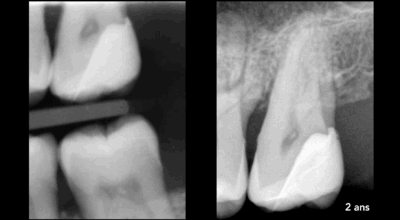

Coiffage pulpaire direct

Si le curetage de la lésion carieuse (schéma du milieu) s’effectue jusqu’à la pulpe dentaire, un biomatériau bioactif (type ciment biocéramique) peut être apposé sur la pulpe exposée.

Schéma de droite : 1 = biomatériau bioactif type ciment biocéramique, 2 = biomatériau de restauration coronaire

Cas clinique

Coiffage pulpaire direct : 90,4% de taux de succès